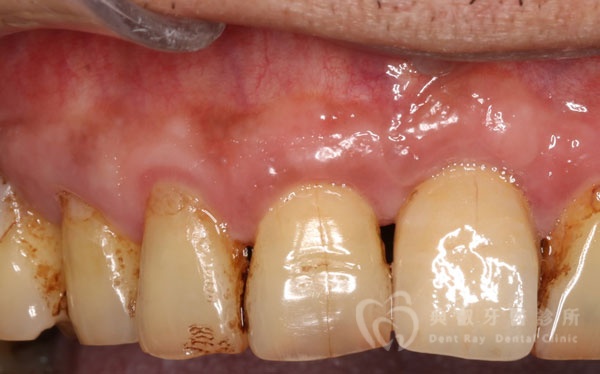

植牙案例四

植牙案例